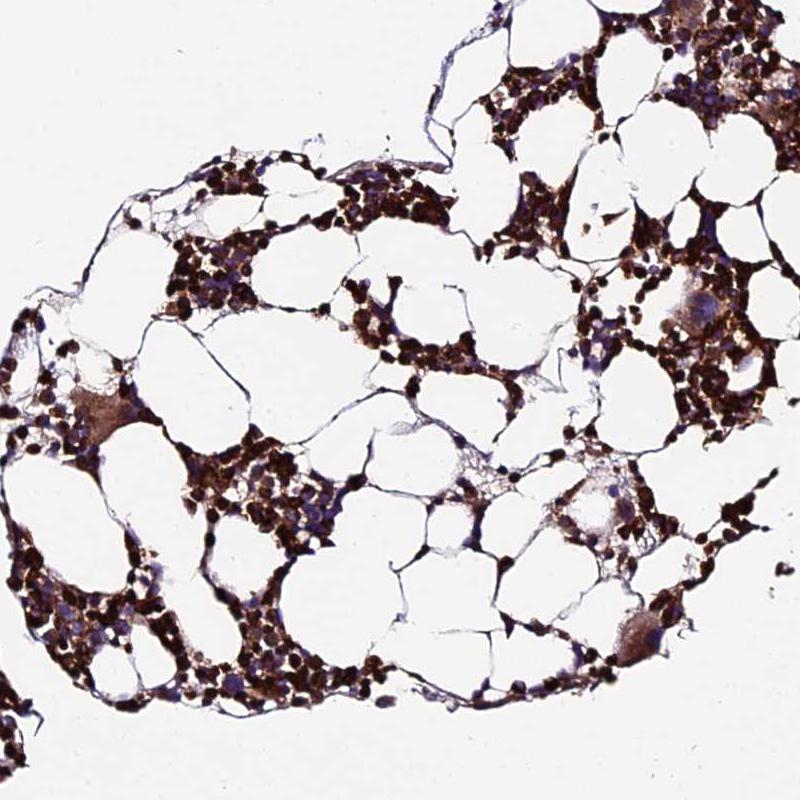

Immunohistochemistry analysis in human bone marrow and skeletal muscle tissues using HPA041564 antibody. Corresponding ABCA7 RNA-seq data are presented for the same tissues.